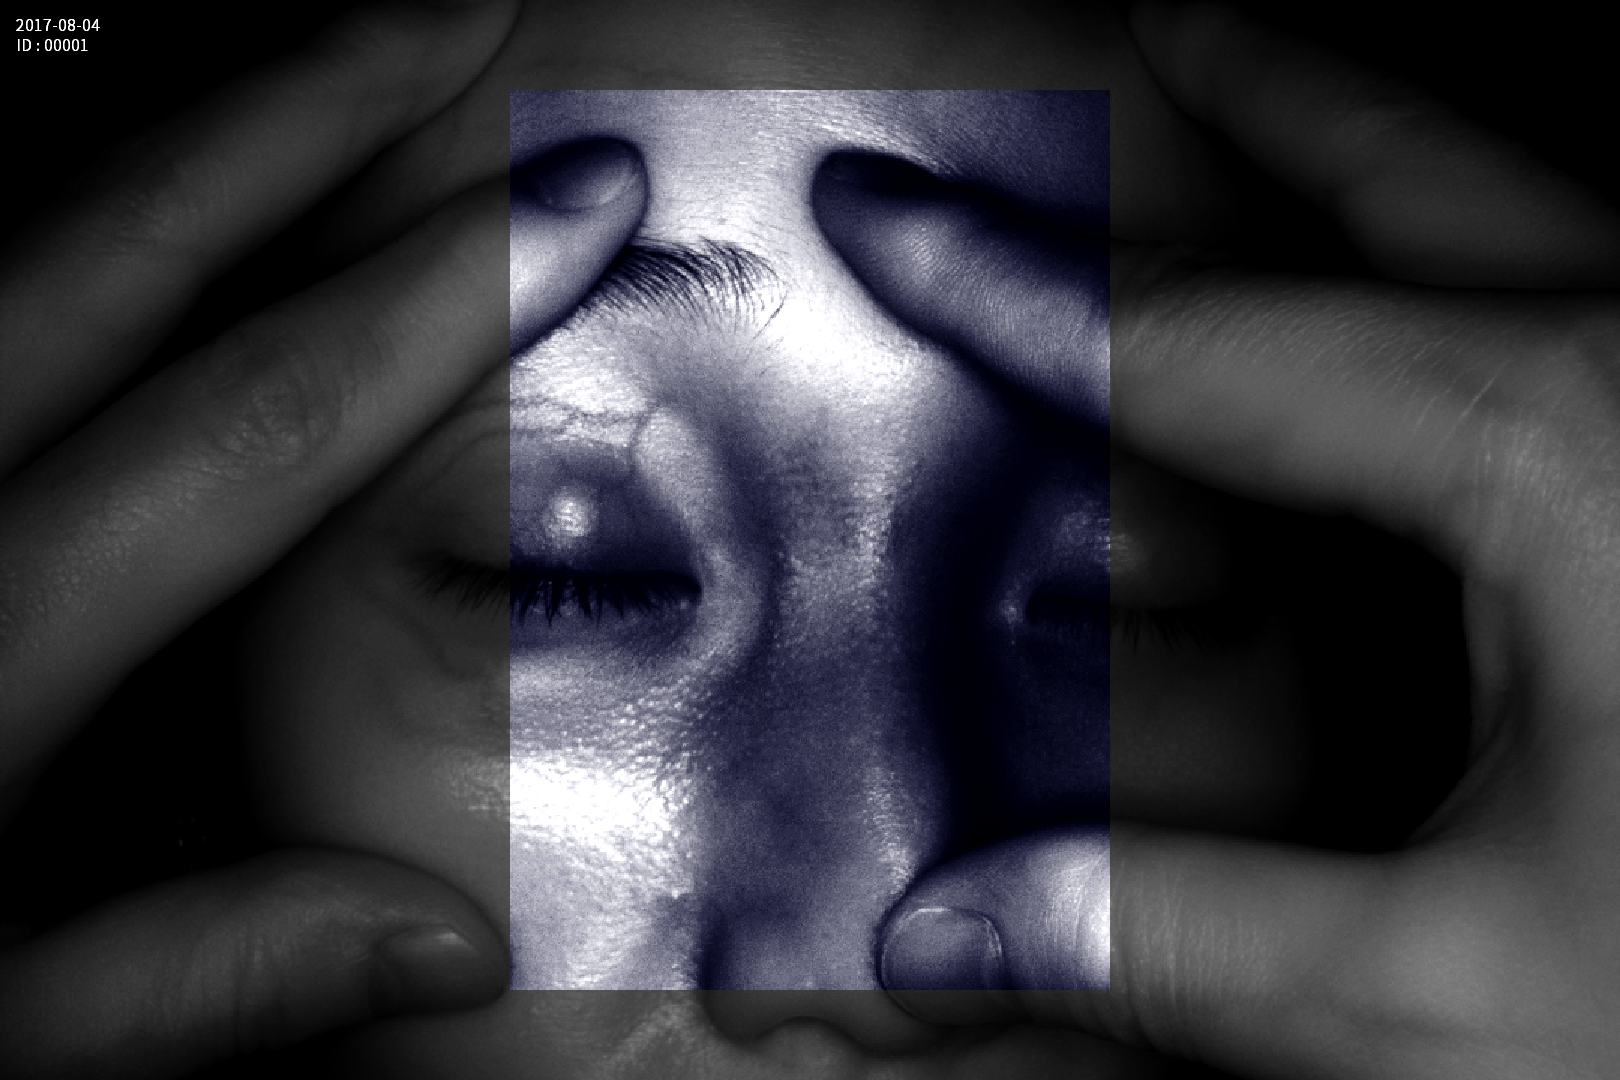

Dispozitiv medical portabil, non-contact, ce ajută la vizualizarea venelor pentru efectuarea puncției venoase, intervențiilor chirurgicale plastice, diagnosticul venelor varicoase.

Grad mare de detecție a venelor greu vizibile până la 10 mm adâncime (inclusiv vene faciale)

Funcție de salvare și comparare imagini înainte și după procedura de tratament vascular

Imaginea venelor este proiectată pe monitorul propriu în timp real si ajută la identificarea corectă și precisă

Multiple aplicații de vizualizare vene atât la sugari cât și la pacienții obezi sau în urgențe indiferent de tonul de culoare a pielii